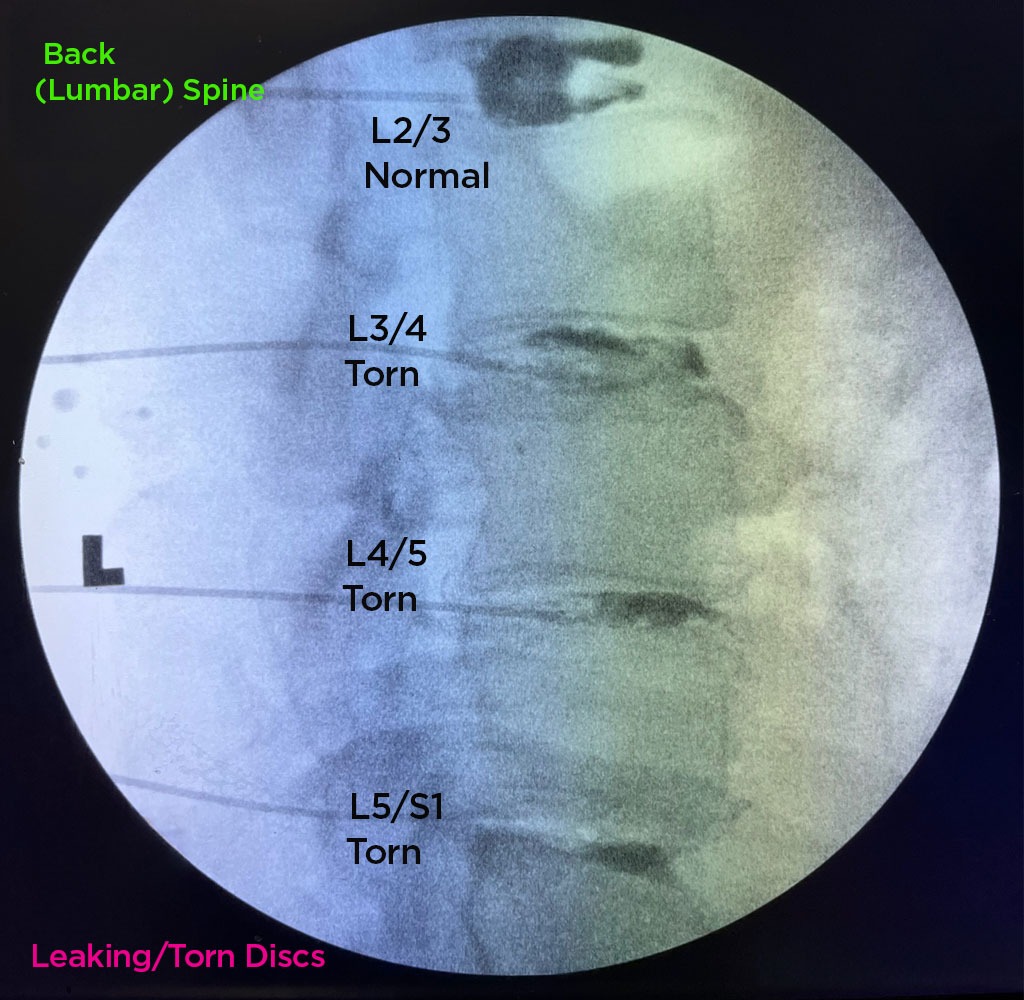

Annulargram™ Gallery

This gallery contains Annulargram images.

The Annulargram is a pain-free test and a crucial part of the DISCSEEL Procedure that identifies even the most subtle tears in spinal discs that MRI and discography cannot.

During the Annulargram, every disc in the region is tested to address current and future pain issues by finding even the most subtle annular tears. With the Annulargram, damaged spinal discs are pinpointed and precisely treated with Fibrin, leaving all healthy discs as they are.

The Annulargram™ and MRI comparison

Figure 01: Comparison of Lumbar spine Annulargram™ and Lumbar spine MRI.

Tears in spinal discs cannot be seen on MRI nor discography. As shown: leaky discs are only visible on the Annulargram.